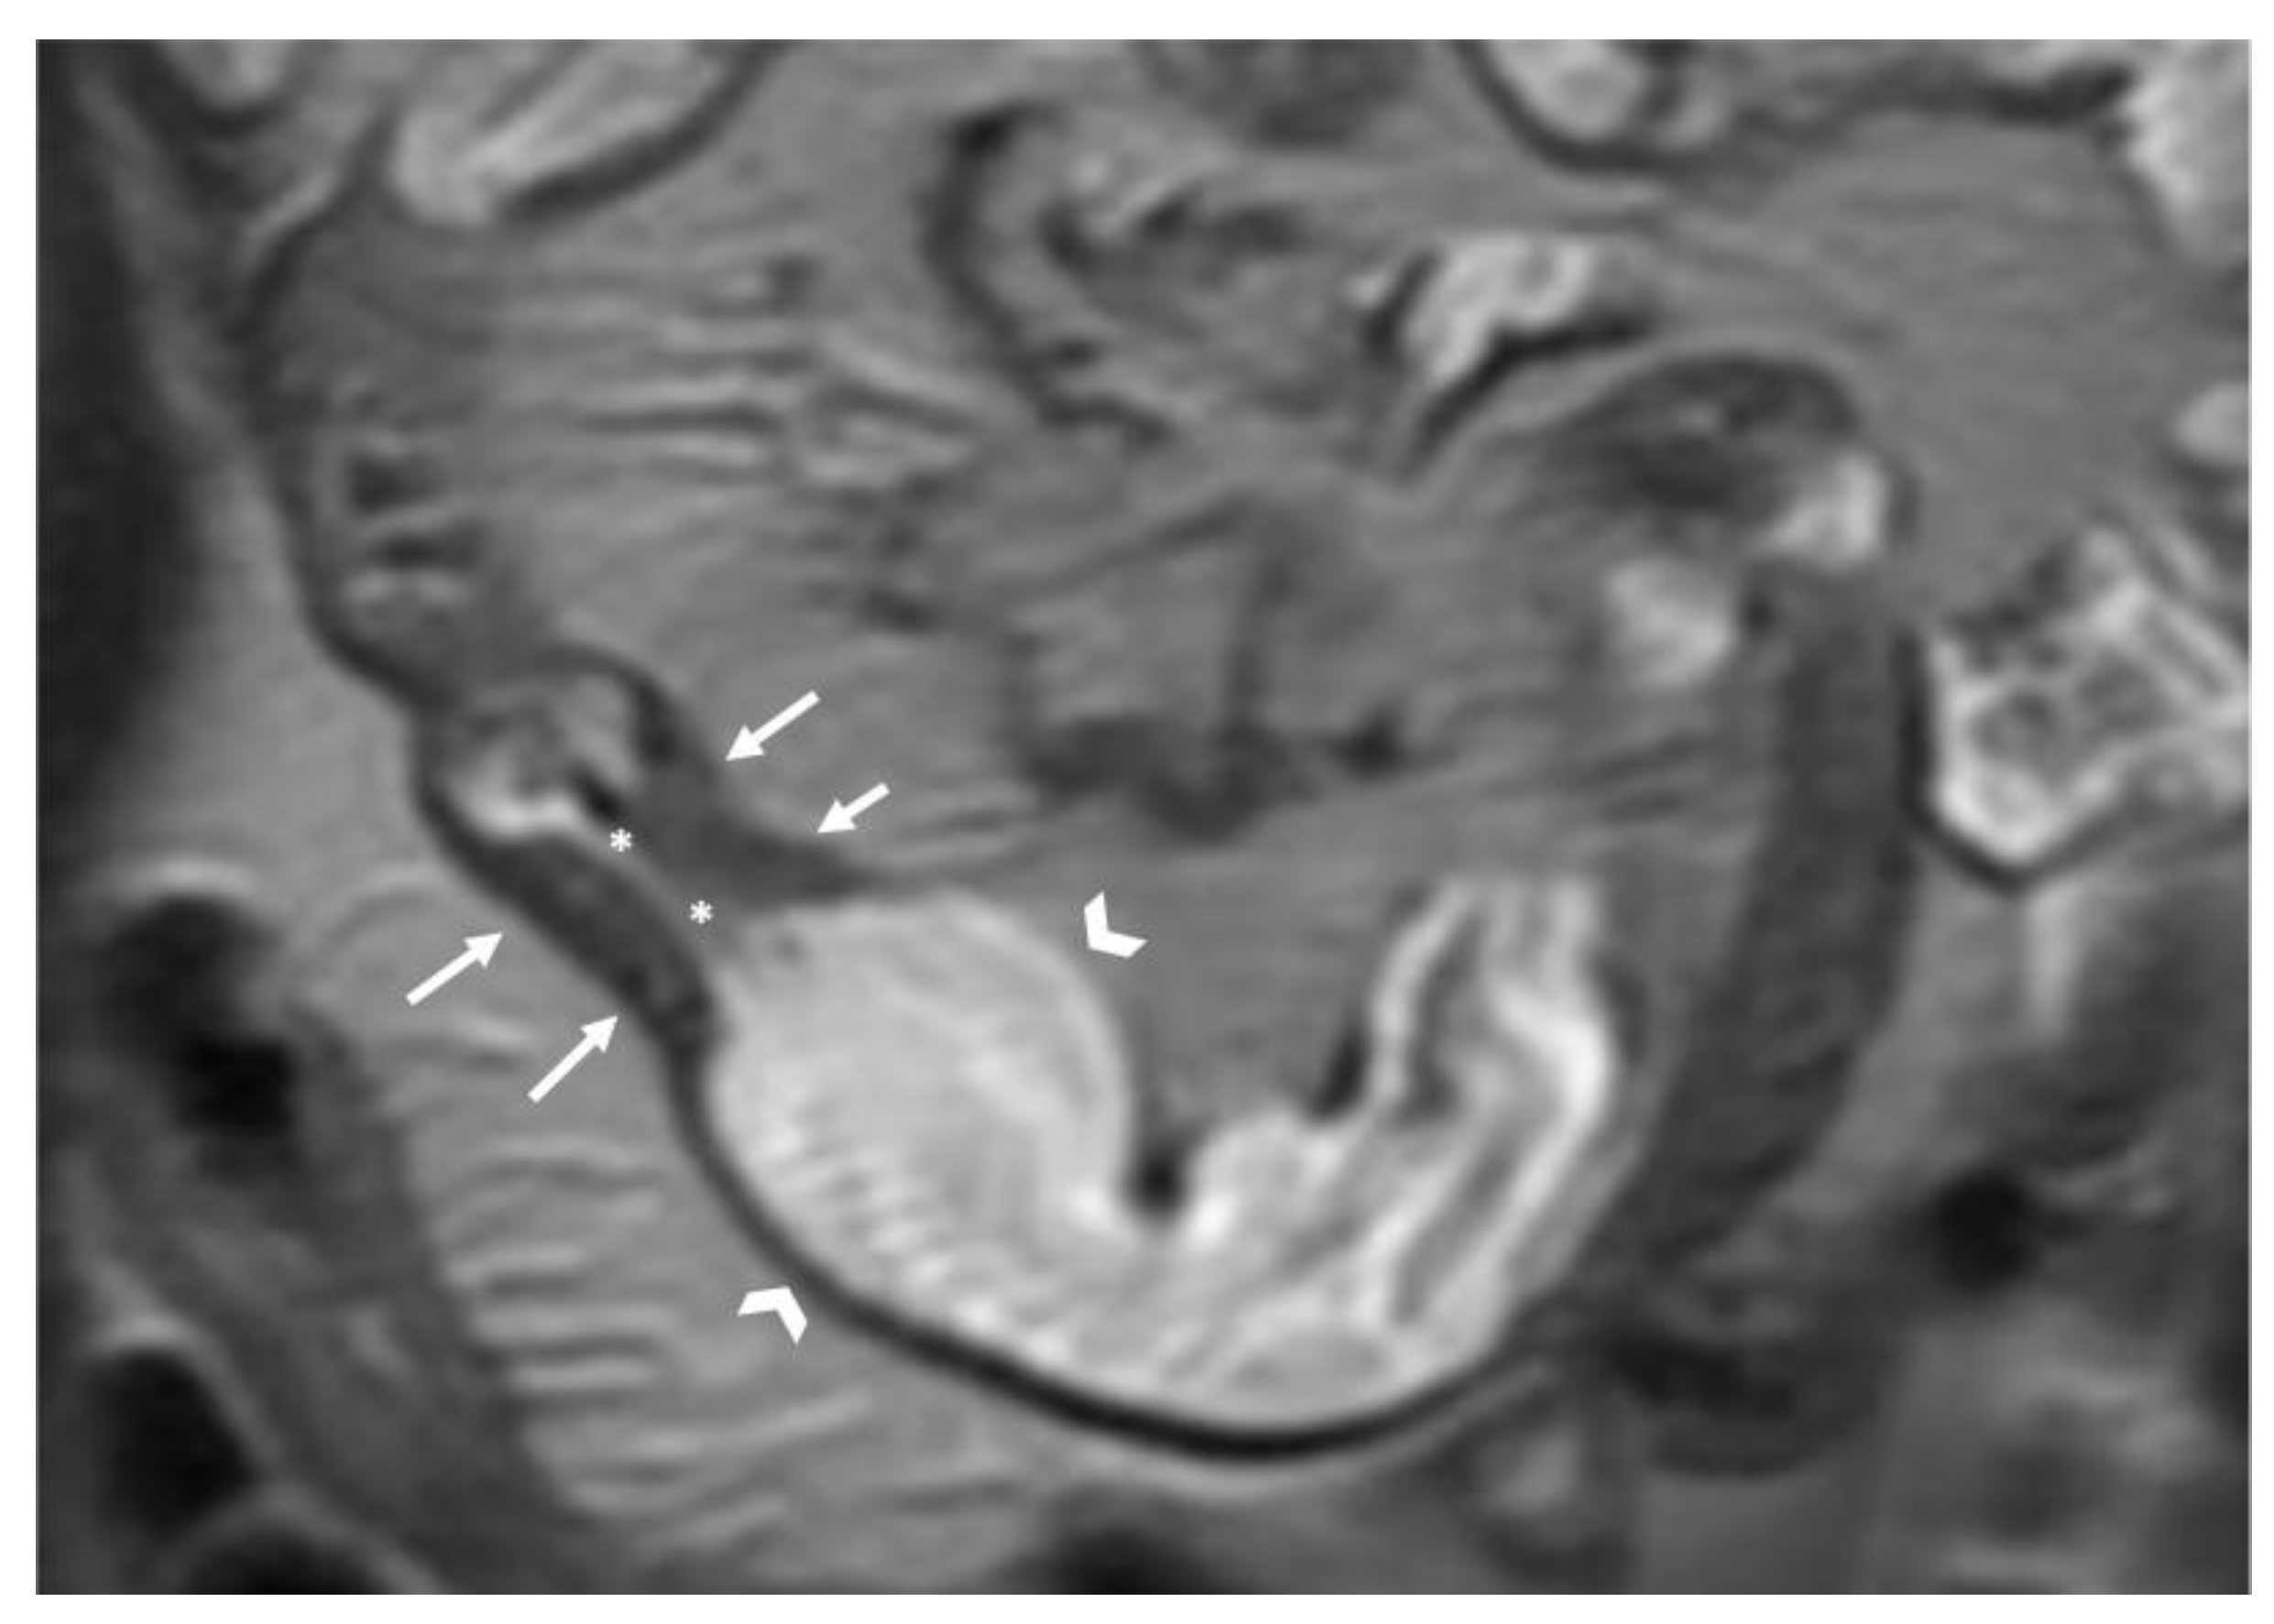

- Fistulae: no, yes. If present, indicate type (entero-enteric, entero-cutaneous, other).

- Sinus tract: no, yes.